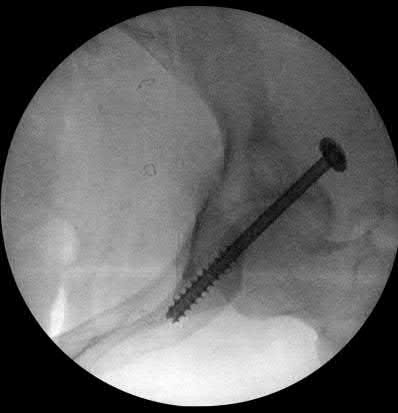

Question 1:

A 12-year-old obese boy presents with vague left thigh and knee pain. He is diagnosed with a Slipped Capital Femoral Epiphysis (SCFE) as seen in similar clinical scenarios. During percutaneous in-situ fixation, unrecognized penetration of the guide wire into the hip joint occurs. What is the most likely specific complication resulting from this technical error?

Correct Answer: Chondrolysis

Explanation:

Chondrolysis is a severe complication of SCFE characterized by rapid destruction of the articular cartilage. While it can occur idiopathically, its most established iatrogenic cause is unrecognized intra-articular hardware penetration. The 'approach-withdraw' fluoroscopic technique is required during pinning to assure pins are entirely intraosseous. Avascular necrosis (AVN) is usually due to damage to the epiphyseal blood supply (retinacular vessels) secondary to the initial displacement, forceful closed reduction, or posterosuperior pin placement.